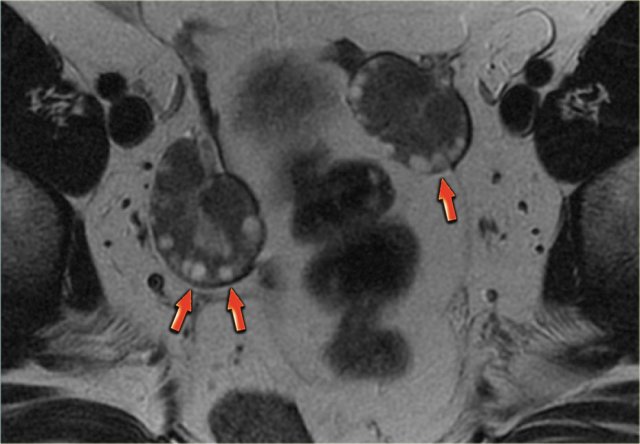

On the axial T2-weighted image both lesions show typical 'shading'.

The gradual drop in T2 is thought to be caused by a combination of increasing viscosity and increasing concentration of protein and iron towards the dependent portion of the lesion.

There is no enhancement on the subtraction image (Post-Gd minus Pre-Gd).

Again, subtraction is useful in cases like this: Gd-induced signal increase over the already very bright pre-contrast image would be very hard to appreciate otherwise.